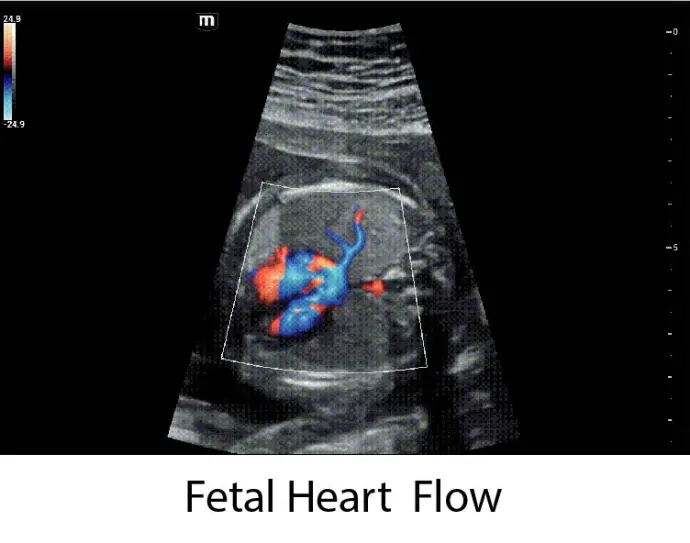

Интелигентно цялостно решение в акушерството - Smart Scene 3D

Иновативна технология при 3D изображенията, при която системата автоматично разпознава анатомичните характеристики на плода в

изображението и извежда бърз достъп до специализираните и оптимизирани визуализации за наблюдаваната анатомична област.